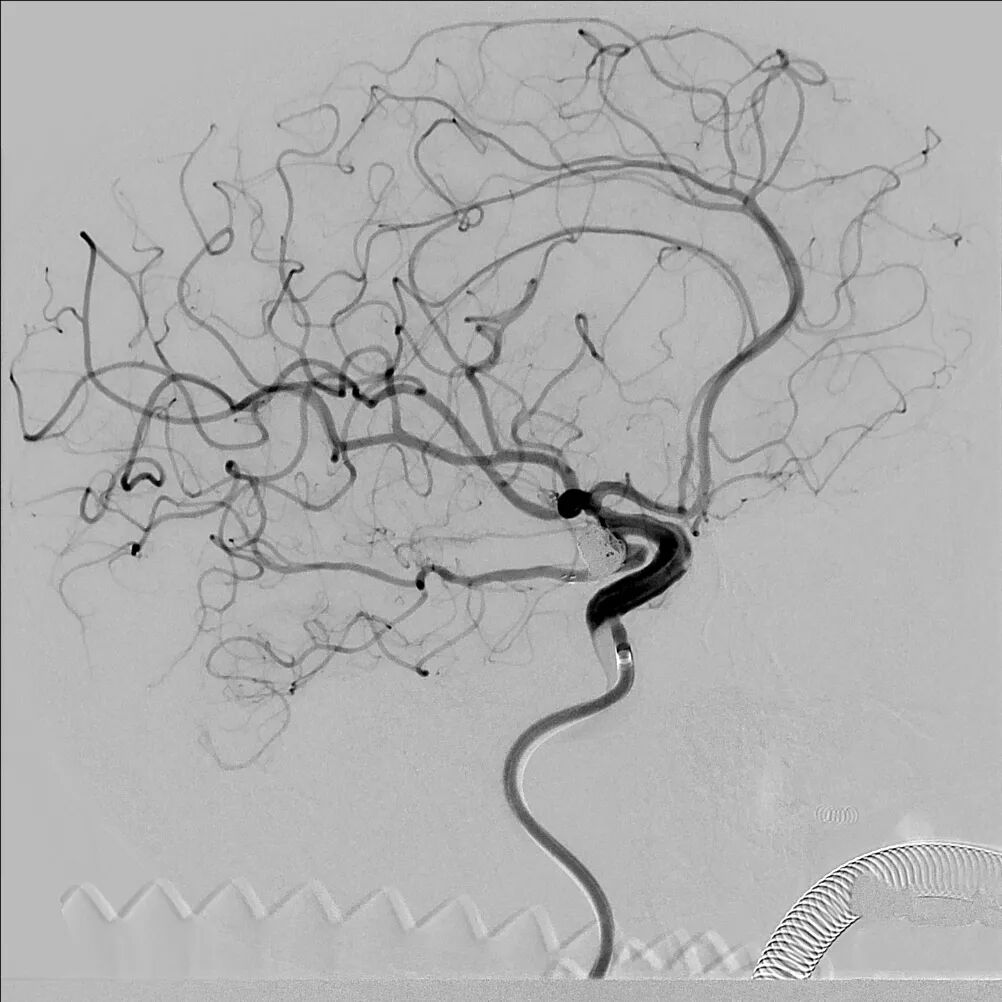

左侧颈动脉正侧位造影:左侧颈内动脉后交通段动脉瘤(箭头所示)。

栓塞动脉瘤:在栓塞动脉瘤过程中血管造影可见后交通动脉均显影,动脉瘤栓塞致密,术中依次使用弹簧圈:使用Target2mm×4cm、Target2mm×4cm、Target2mm×4cm栓塞子瘤,再使用多枚弹簧圈补充栓塞瘤体。

栓塞动脉瘤:在栓塞动脉瘤过程中血管造影可见后交通动脉显影,动脉瘤栓塞致密。

术后即刻造影:后交通动脉瘤致密栓塞,后交通动脉及颈内动脉保护良好。